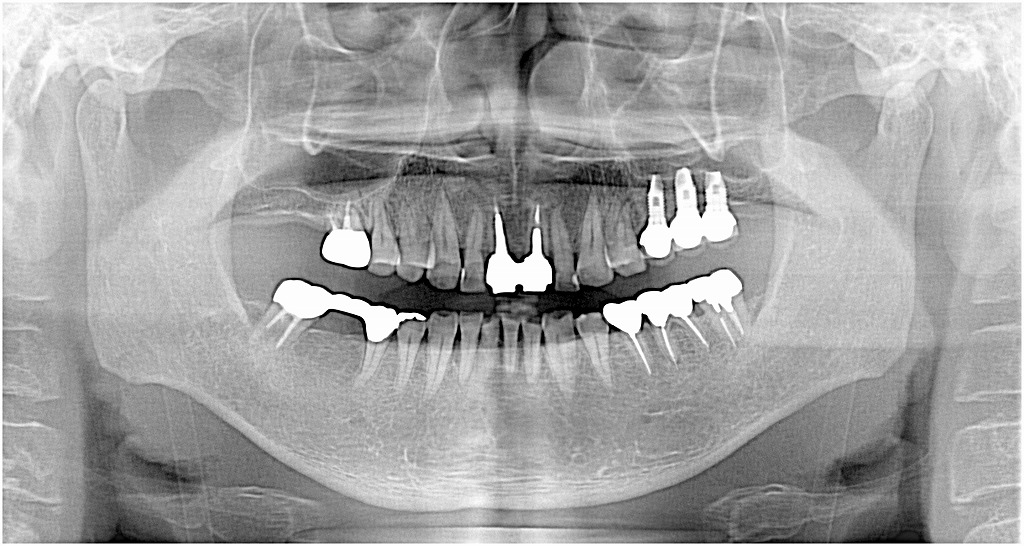

3本インプラント埋入時になります

下顎が伸びてきてインプラント部の歯を歯を建てるのに

平べったい歯しか入らない状態

残念ですが、、、下顎を神経の処置を行いしっかりとした

咬合高径の歯を入れていきます

機能時のパノラマになります